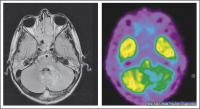

Abbildung 4: Positronen-Emissions-Tomographie (PET) nach i.v.-Applikation von 370 MBq 18F-Fluor-Deoxyglykose (FDG): Substanzdefekt linkscerebellär.

PET

Abbildung 5: Single Photon Emission Computed Tomography- (SPECT-) Szintigraphie des Gehirns 10 min. nach i.v.-Applikation von 555 MBq 99m-Tc- NEUROLITE): Inhomogen abgeschwächte Anreicherung am Großhirnkortex beidseits.

SPECT-Szintigraphie